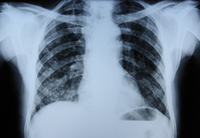

Assessment of persistent pulmonary infiltrate

Posterior-anterior chest x-ray in Pneumocystis jiroveci pneumonia showing severe, bilateral pulmonary interstitial infiltrates with pneumatocoeles

From the collection of Matthew Gingo, UPMC